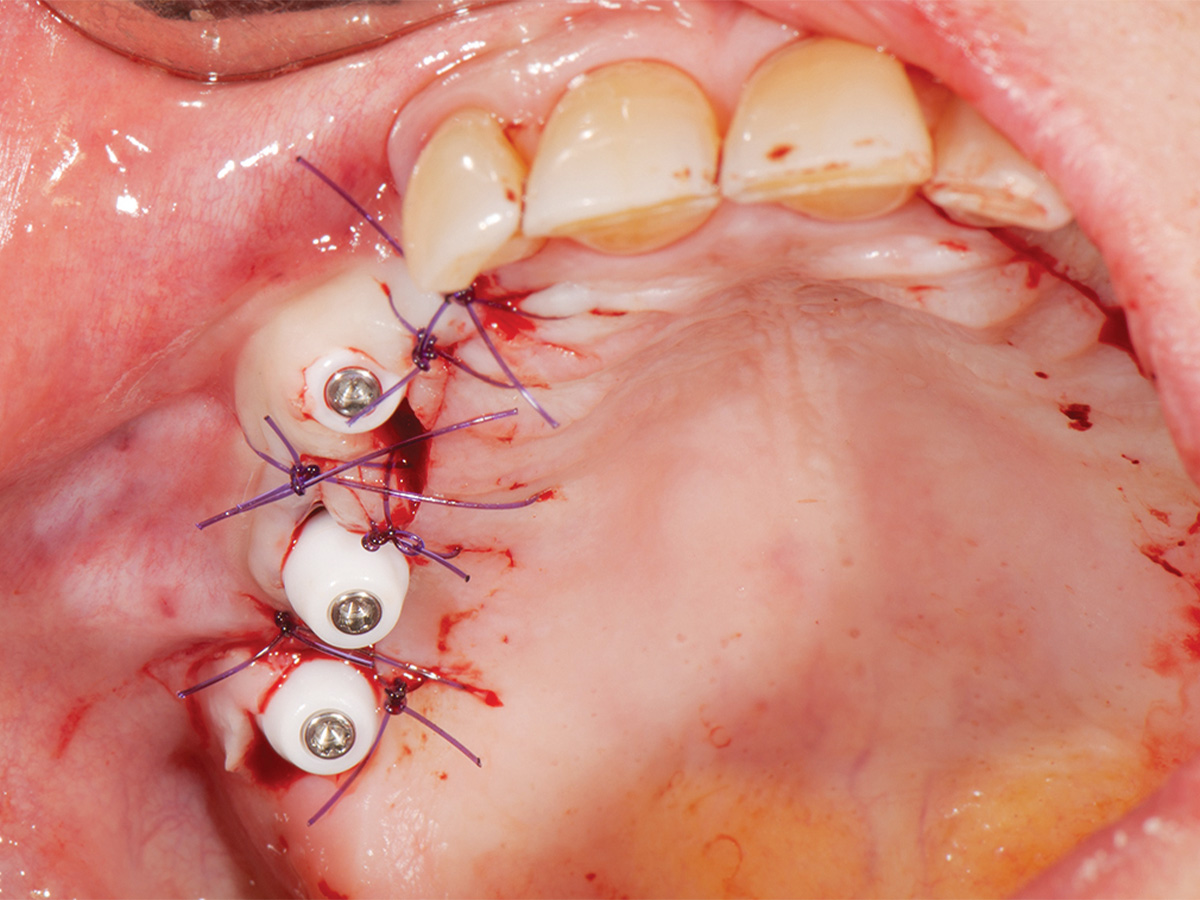

Abbildung 7

Einsetzen der Gingivaformer nach vier Monaten.